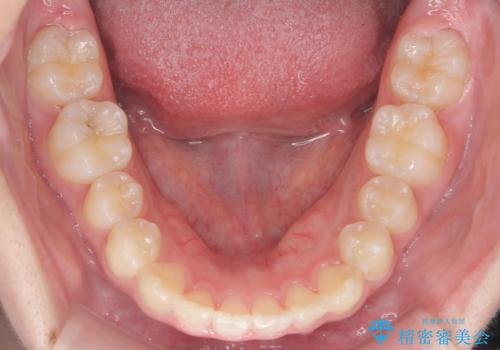

子供の出っ歯 生え代わりと成長期を利用して非抜歯で矯正

- 出っ歯を主訴に来院。

生え代わりを待ってから矯正を始めました。

特に右側のかみ合わせがずれていたため、上の奥歯を後ろに下げています。

下顎も前方に成長し、前歯のかみ合わせも同時に深かったのを浅くすることができました。

矯正は成人でも可能ですが、成人矯正よりも、有利なことがたくさんあります。

10代で矯正を行うと歯の動きも動きやすく、骨の付いてくる度合いもとてもよく、歯肉退縮など副作用が少ないのでお勧めです。移動も早いため、矯正治療期間も短めです。